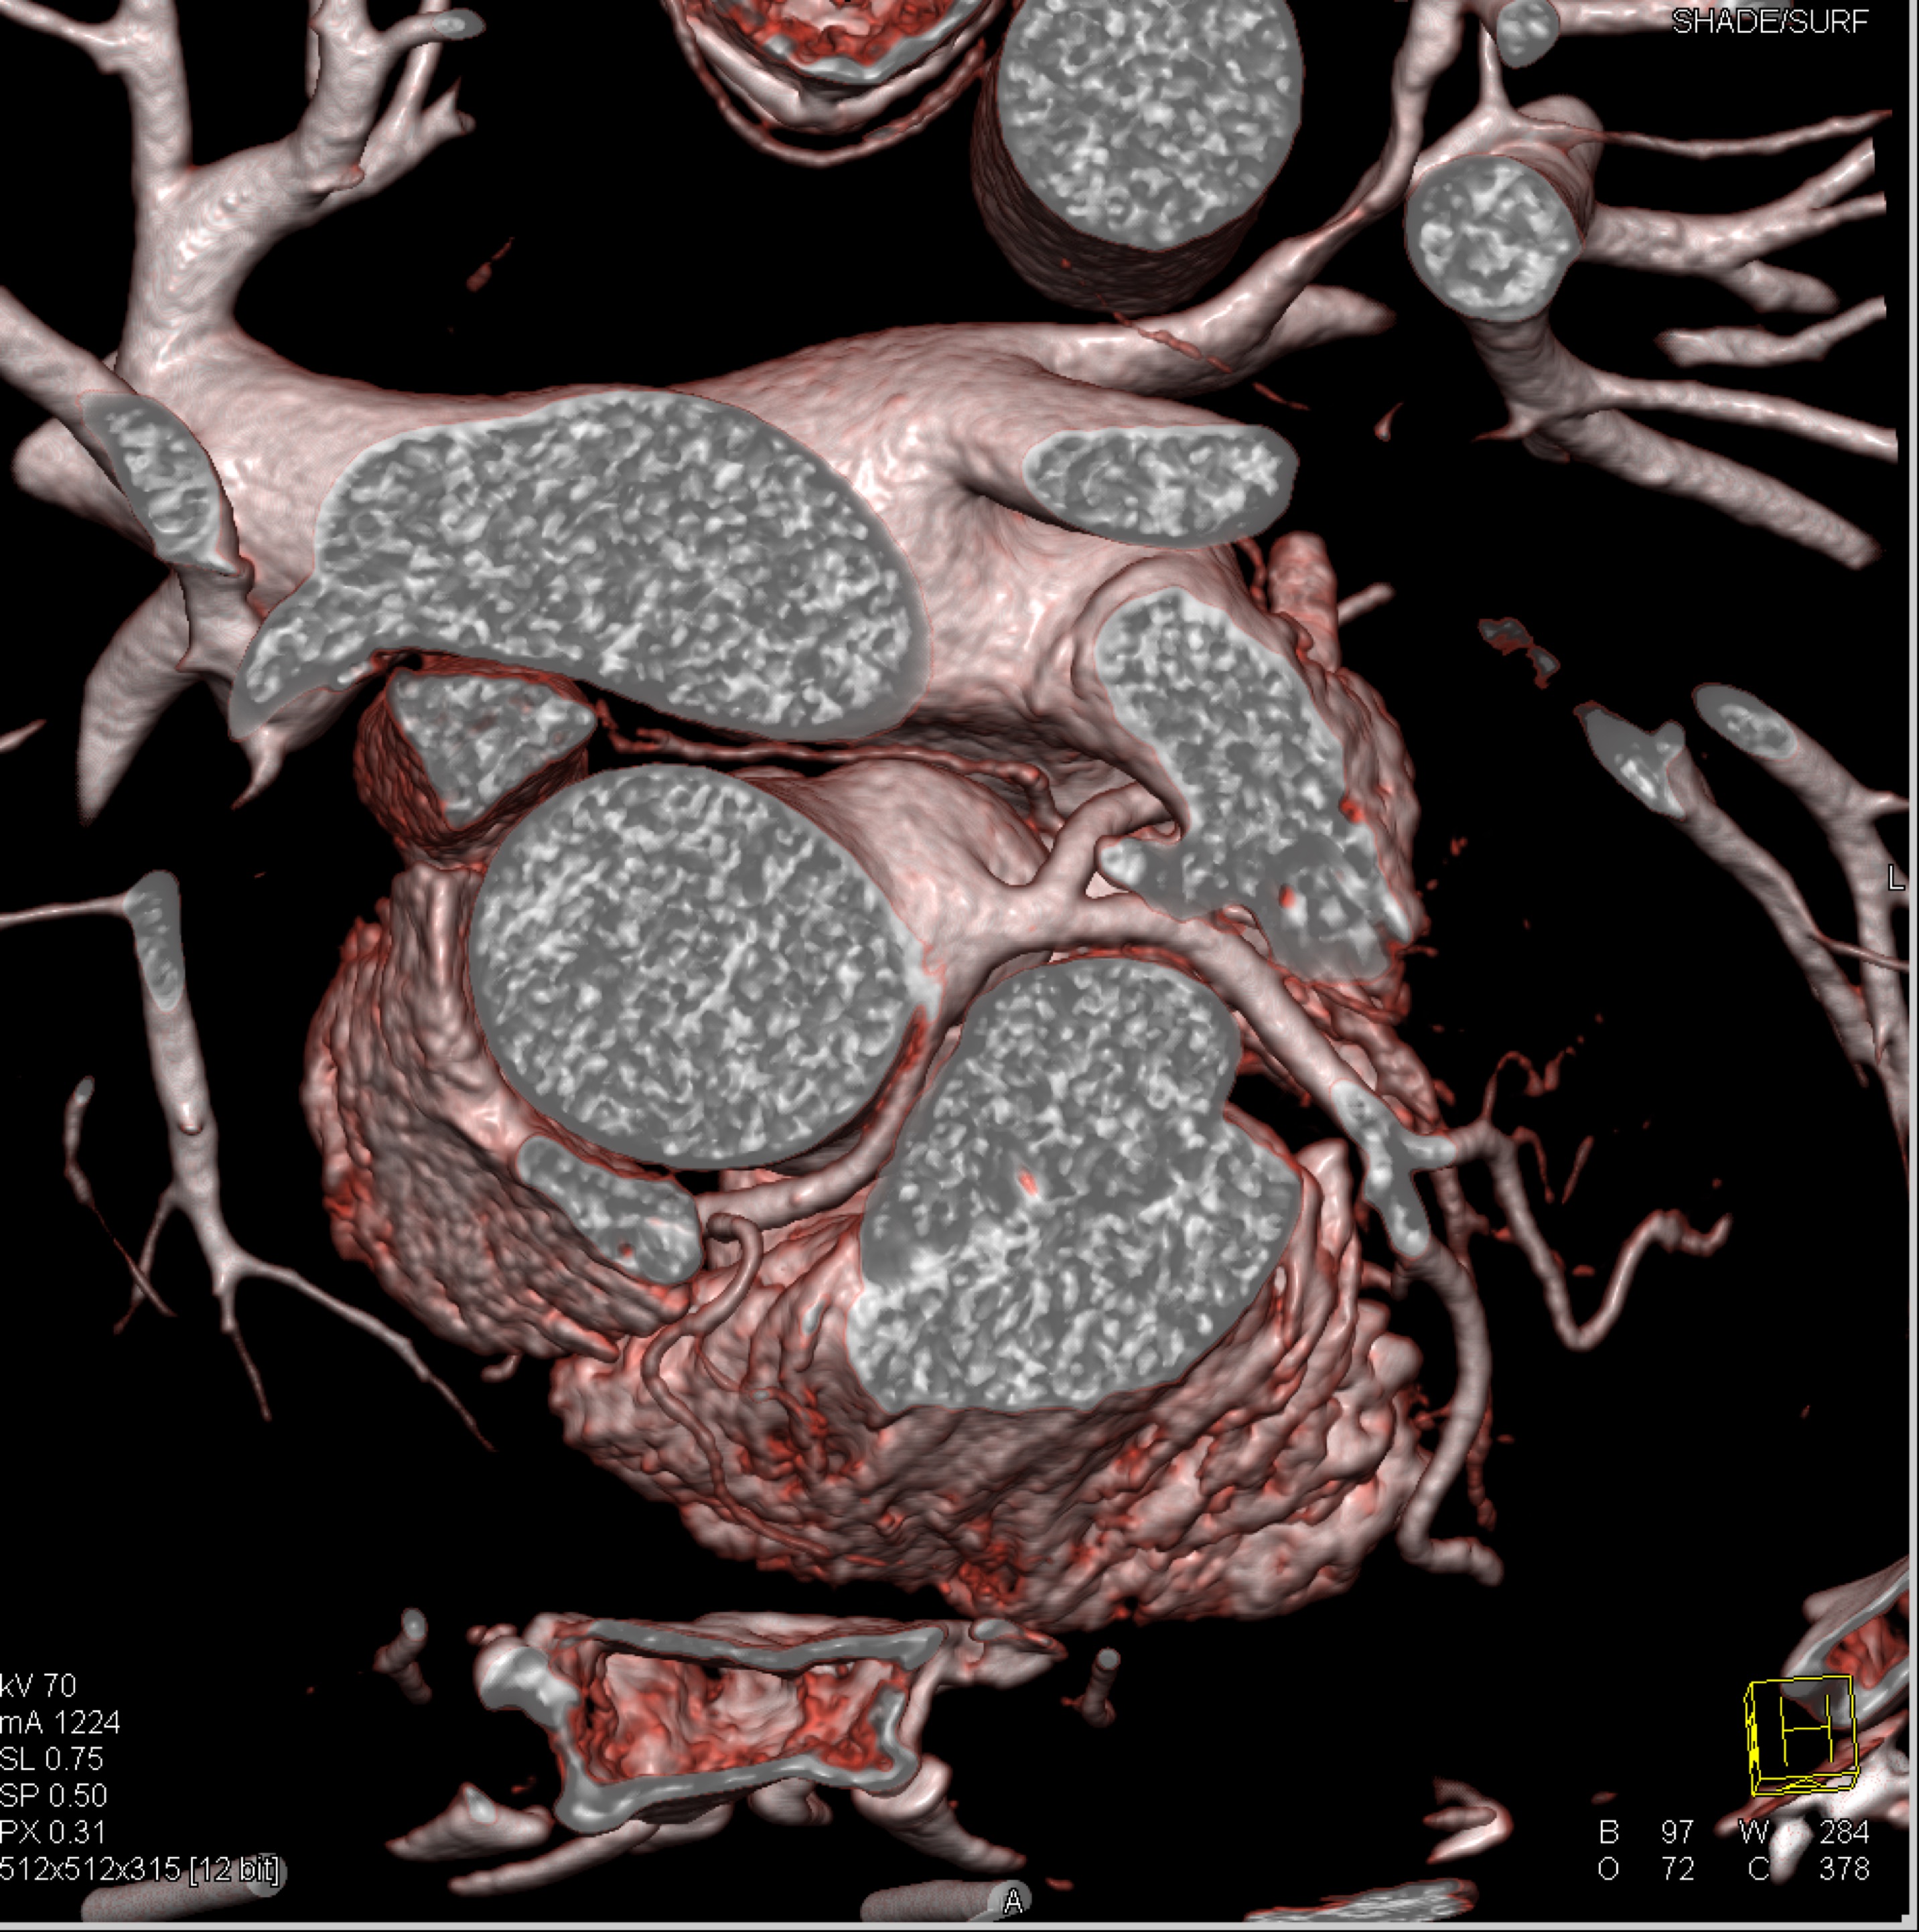

8) In this patient with RUQ pain and no history of trauma the best diagnosis is?

multiple hemangiomas

focal nodular hyperplasia

hepatic adenomas

angiosarcoma of the liver